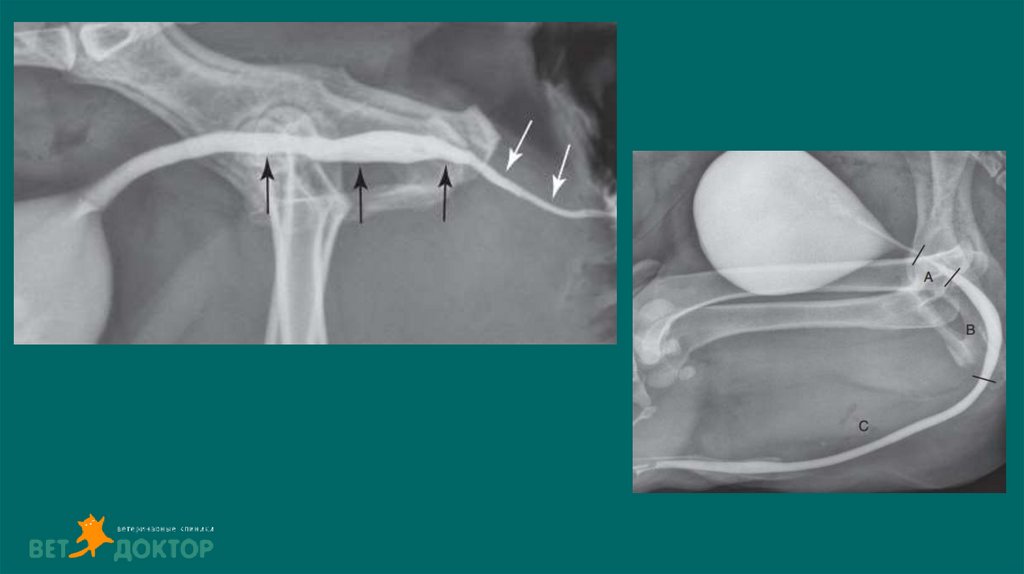

13. Позитивно-контрастная цистоуретрограмма

Показания:

Определение размера, формы и расположения мочевого пузыря

Определение проходимости или разрыва мочевого пузыря или уретры.

Обнаружение дефектов наполнения, связанных с уролитами (цистины/ураты) или гематомами,

выявления полипов или новообразований.

ПОДГОТОВКА

• Установка стерильного мочевого катетера для введения контраста

• Получение обзорных боковых и ВД снимков

• Введение стерильного йодсодержащего контраста в расчете 10мл/кг( разбавлен стерильным

физ.раствором 1:2 или 1:5)

• Выполняем латеральные/ВД снимки немедленно после введения контраста .

• Для получения уретрограммы оттянуть дистально катетер, ввести контраст одновременно сделать

боковой снимок ,провести серию снимков.

• Удаление контраста из мочевого пузыря по завершению

18. карцинома простаты